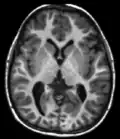

T1 e T2

Cada tecido retorna ao seu estado de equilíbrio após a excitação pelos processos independentes de T1 (spin-tretice) e T2 (spin-spin) de relaxamento. Para criar uma imagem ponderada em T1, a magnetização pode ser recuperada antes de medir o sinal MR, alterando o tempo de repetição (TR). Esta ponderação de imagem é útil para avaliar o córtex cerebral, identificando tecido adiposo, caracterizando lesões focais e, em geral, para obter informações morfológicas, bem como para imagens pós-contraste. Para criar uma imagem ponderada em T2, a magnetização pode decair antes de medir o sinal MR alterando o tempo de eco (TE). Esta ponderação de imagem é útil para detectar edema e inflamação, revelando lesões de substância branca e avaliando a anatomia zonal na próstata e no útero.

A exibição padrão de imagens de MRI é representar características de fluido em imagens em preto e branco, onde diferentes tecidos são os seguintes:

| Sinal | T1-ponderado | T2-ponderado |

|---|---|---|

| Alto | ||

| Intermediário | Matéria cinzenta mais escura que matéria branca | Matéria branca mais escura do que a matéria cinzenta |

| Baixo |

Sequências

Uma sequência de RM (Ressonância Magnética) é uma configuração particular de pulsos de radiofrequência e gradientes, resultando em uma imagem específica.[65] O ponderamento T1 e T2 também podem ser descritos como sequências de RM.

| Grupo | Sequência | Abreviatura | Física | Distinções clínicas principais | Exemplo |

|---|---|---|---|---|---|

| Eco de spin | Ponderado em T1 | T1 | Medição da relaxação spin-lattice usando um tempo de repetição (TR) curto e tempo de eco (TE) curto. |

Base padrão e comparação para outras sequências. |

|